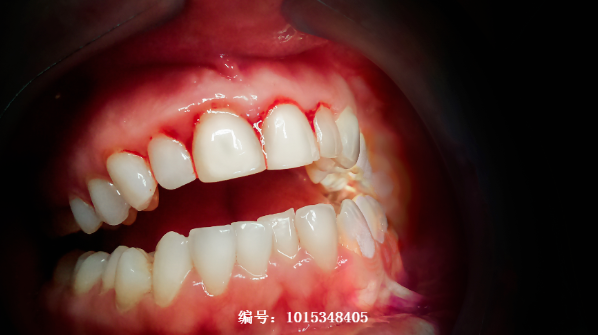

一般来说,早期出现的症状是牙龈出血。毛细血管受到了炎症刺激后容易破裂,牙刷刷牙或者咀嚼食物时就会出现明显的出血。此外,牙龈发红肿胀、易于疼痛也是牙周病的常见症状。如果不及时治疗,牙周病还会引起口臭、牙齿松动、牙齿脱落等更为严重的后果。